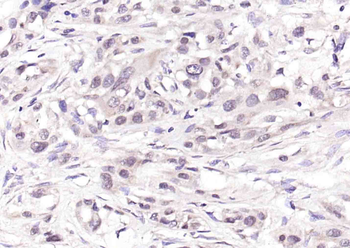

Phospho-CDKN1A/p21 (Thr145) Rabbit Polyclonal Antibody [orb6568]

FC, IF, IHC-Fr, IHC-P

Mouse, Rat

Human, Mouse, Rat

Rabbit

Polyclonal

Unconjugated

100 μl, 50 μl, 200 μlPhospho-CDKN1A/p21 (Ser130) Rabbit Polyclonal Antibody [orb6571]